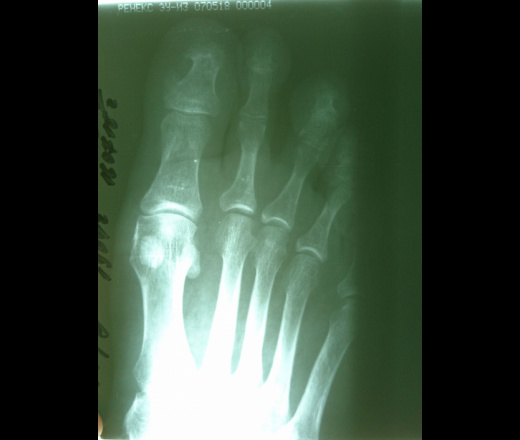

Синостоз первой пястной кости: причины и последствия